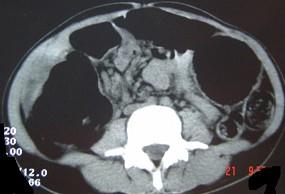

女,30岁,便秘、腹痛腹胀多年,CT检查如图,最可能的诊断是 ( )A.结肠肠梗阻B.先天性巨结肠C.结肠肠套叠D.结肠肠扭转...

问题 女,30岁,便秘、腹痛腹胀多年,CT检查如图,最可能的诊断是 ( )

选项 A.结肠肠梗阻 B.先天性巨结肠 C.结肠肠套叠 D.结肠肠扭转 E.结肠肠栓塞

答案 B